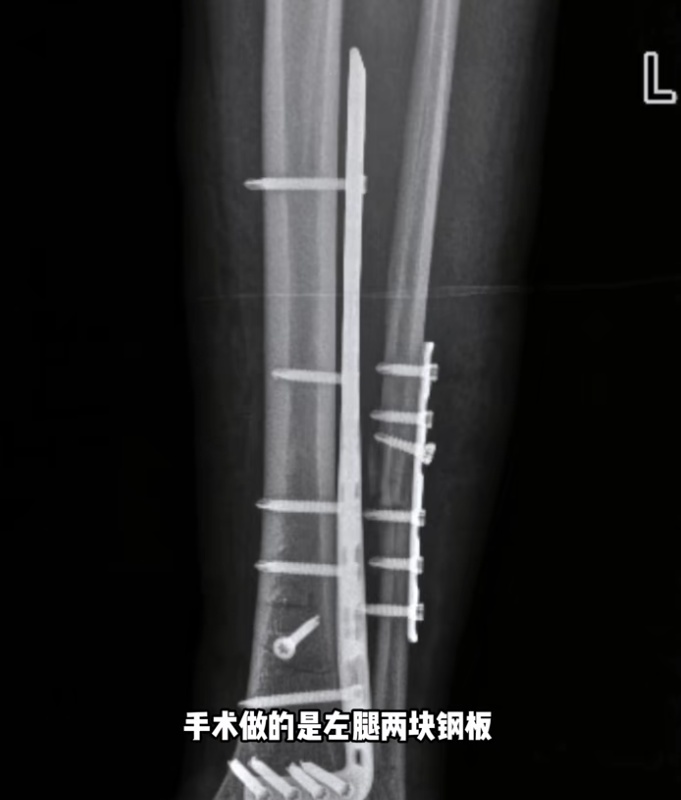

千一称在新疆接受手术,左腿2块钢板16颗钉子,右腿2条髓内钉和6颗固定钉子,缝了45针。